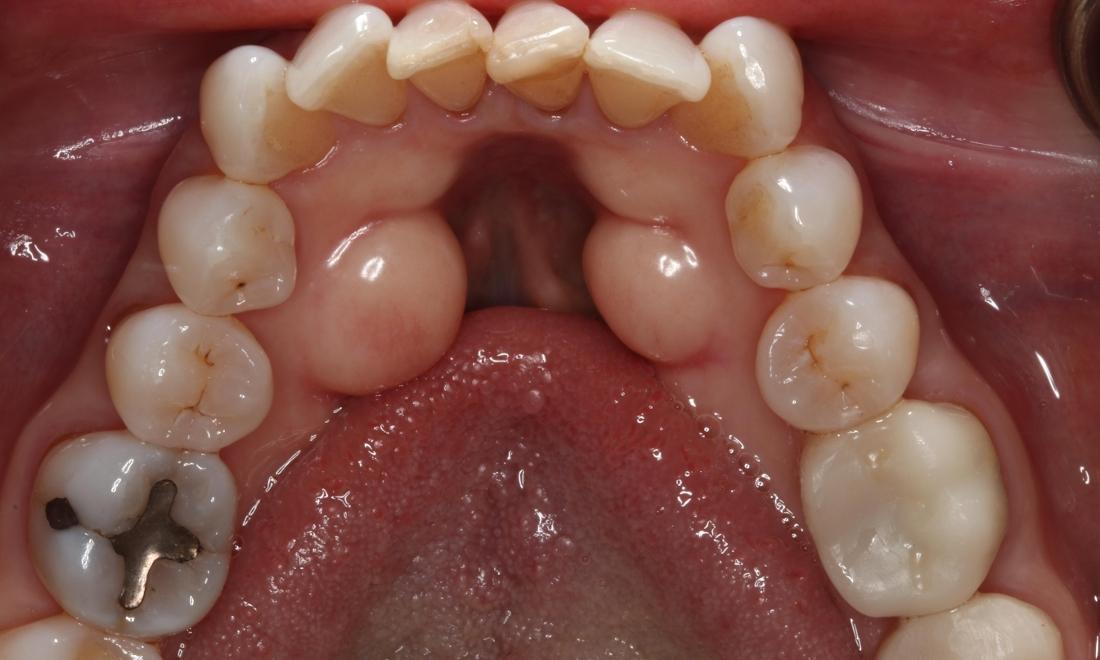

Patient before Lingual Tori Removal Patient after Lingual Tori treatment in Brentwood, TN